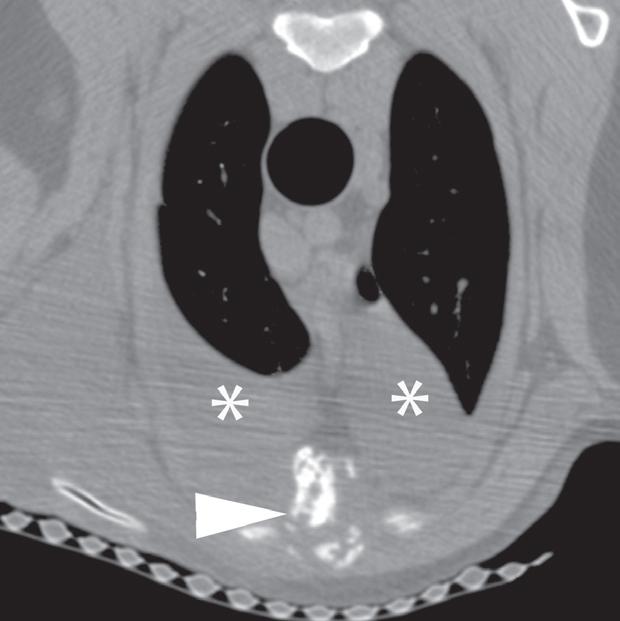

Rycina 4.1.5. Osteomyelitis mostka (pies) TK

Badanie wykonano u 18-miesięcznego, kastrowanego samca dobermana. Ryciny a i b przedstawiają kolejne obrazy poprzeczne doczaszkowej części klatki piersiowej w orientacji doczaszkowo-doogonowej. Widoczne jest nieuorganizowane niszczenie kości obejmujące drugi segment mostka (a–d – grot strzałki). Obecne jest również złamanie patologiczne (c – grot strzałki). Obustronnie widać umiarkowaną ilość płynu w jamie opłucnej w zgodnej grawitacyjnie przestrzeni opłucnowej (a, b – gwiazdki). Biopsja kości potwierdziła przewlekłe neutrofilowe zapalenie kości i szpiku, a cytologia płynu opłucnowego wykazała obecność zapalenia ropnego